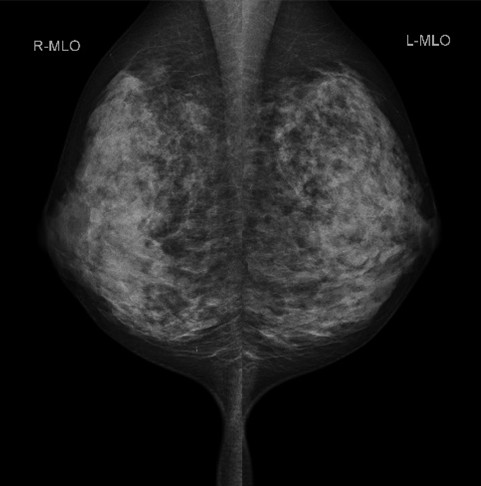

乳房撮影装置(マンモグラフィ)

マンモグラフィ(MMG)とは、乳房専用のX線撮影のことです。乳房を圧迫して撮影するため痛みを伴う場合が多いですが、乳房を薄くして撮影することにより被ばくが軽減し、きれいな画像を得ることが出来ます。そのため検査を受けられる方のご理解、ご協力がとても大切になります。当院の装置は3Dマンモグラフィ(トモシンセシス)が撮影できる装置を導入しております。従来と比べて高精細な画像が得られるようになりました。診察にあたっても5Mの高精細モニターを使用しています。

また当院では「検診マンモグラフィ撮影認定診療放射線技師」が在籍しており、検査は女性技師が担当いたします。